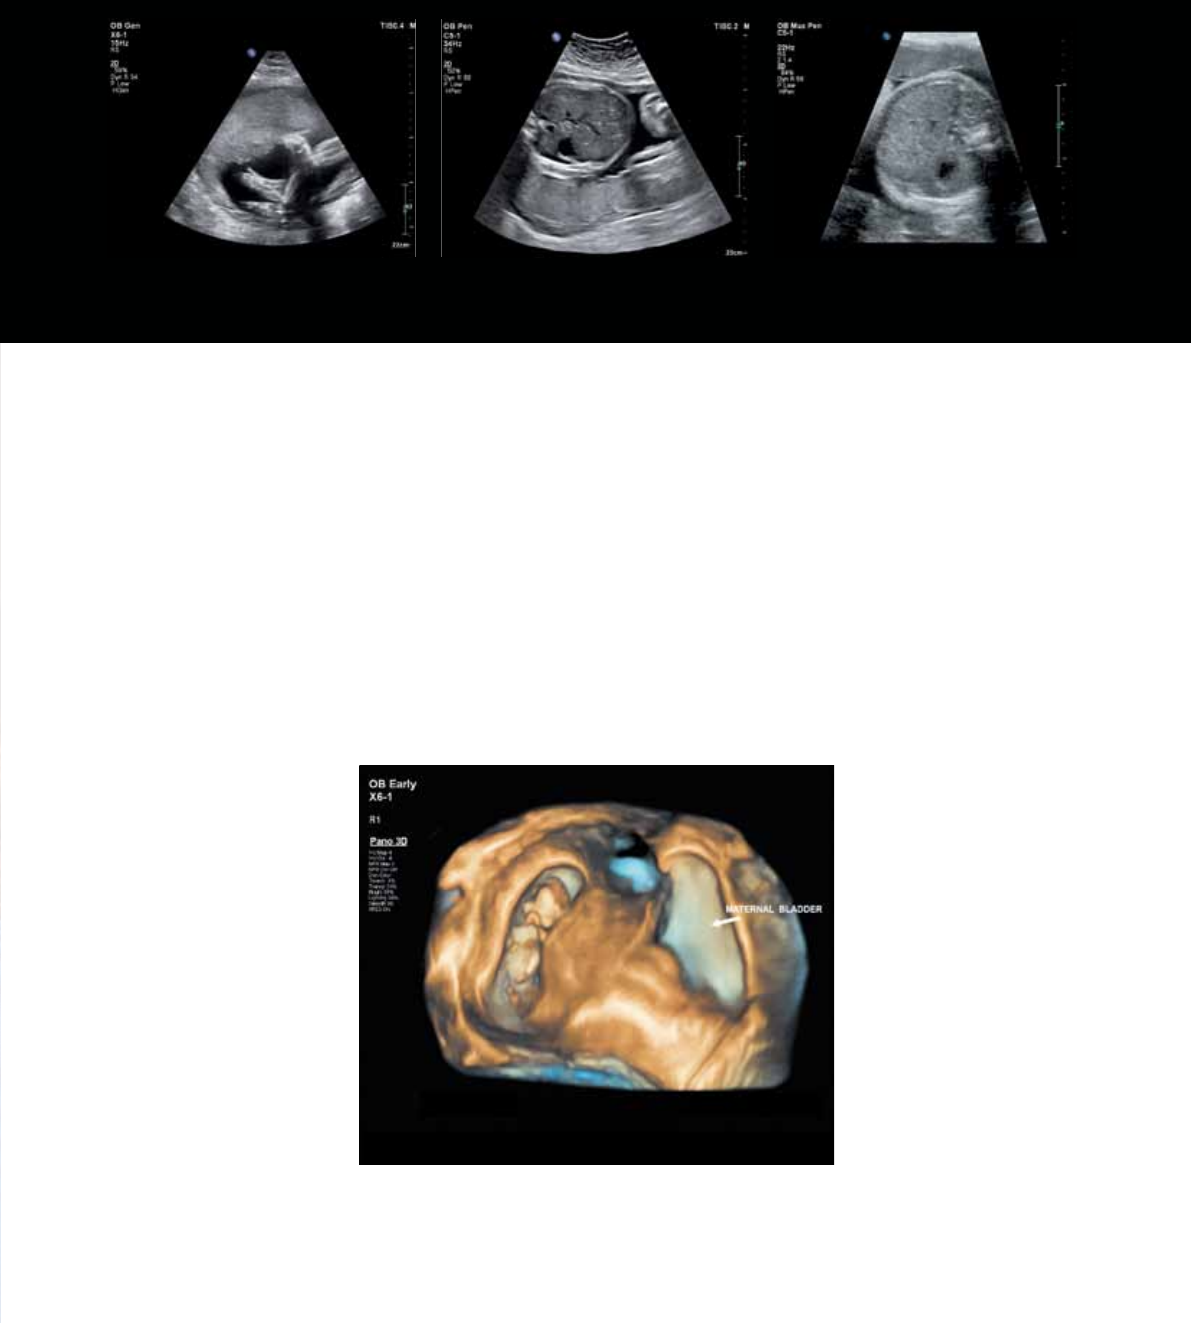

22-week fetus, 3D panoramic image

Exclusive panoramic volume imaging with xMATRIX

Panoramic volume imaging uses Live xPlane imaging

to acquire a calibrated volume over an extended eld of

view. Easily capture, visualize, and quantify 3D panoramic

volumes. For the rst time, you can capture an entire third-

trimester fetus or an entire uterus in one 3D panoramic

volume. Now have exceptional demonstration of the spatial

relationships between structures when a single volume is not

enough to capture the entire Region of Interest, get a global

perspective of the examination area to easily and quickly

identify target structures.

Fetal foot

25-week gestation, BMI = 40

Fetal abdomen, technically

difficult patient, BMI = 80

Fetal abdomen

30-week gestation, BMI = 40.1